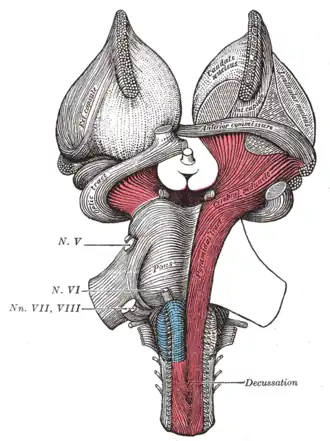

Superficial dissection of brain-stem. Ventral view.

Superficial dissection of brain-stem. Ventral view. -